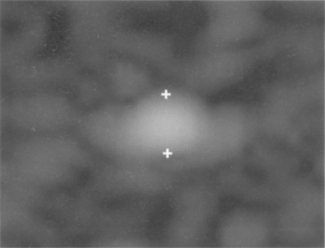

The gray scale processing and therefore dynamic range of an ultrasound system can be assessed by using a suitable test phantom which typically consists of a group of targets which have varying contrasts relative to the background. An example of a typical test phantom is shown in Figure 13.11, and consists of a number of cylinders (which are imaged in cross-section) filled with a material of different scattering strengths to create areas of known and varying gray levels and echogenicity. Figure 13.12 shows an image using such a phantom to assess a system’s dynamic range. This is estimated from the difference between the brightest and darkest regions which can be imaged simultaneously.

image

Fig. 13.12 Ultrasound image using such a test phantom to assess dynamic range